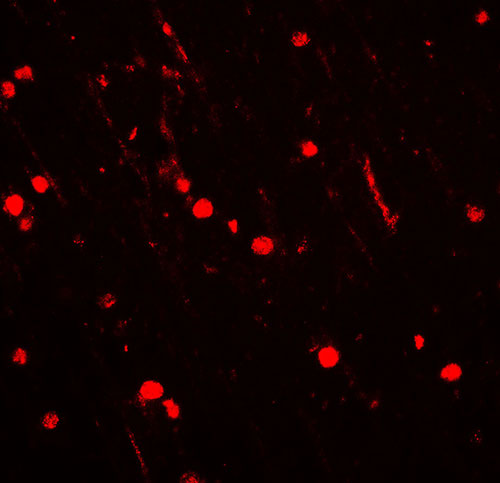

Immunofluorescence of NOX2 in rat brain tissue with NOX2 antibody at 20 μg/ml. |